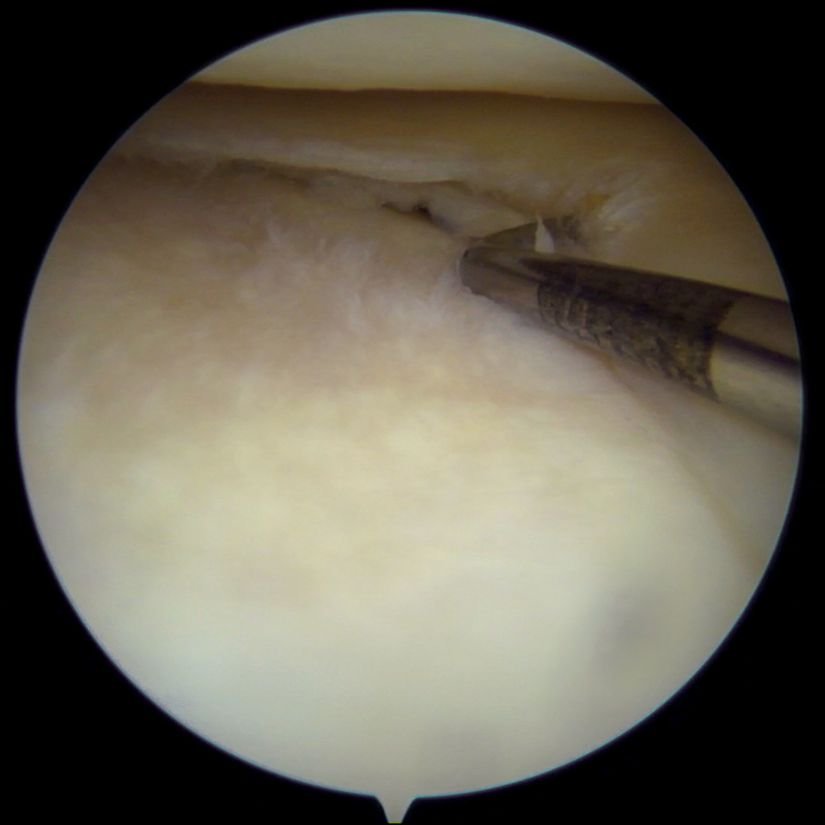

At London Knee Care, we provide expert diagnosis and treatment for meniscal tears — injuries to the C-shaped cartilage that cushions and stabilises the knee joint. The meniscus can tear due to a sudden twist, sports injury, or gradual wear and tear over time. When damaged, it can cause pain, swelling, locking, and difficulty moving the knee smoothly.

We use advanced imaging and minimally invasive keyhole surgery to repair or remove damaged tissue when needed. With precise assessment and guided rehabilitation, we help patients regain comfort, mobility, and confidence in everyday activities.

At London Knee Care, we perform detailed examinations and MRI scans to confirm the presence and type of meniscal tear. Our specialists then tailor a treatment plan to your needs — whether conservative management or surgical repair — ensuring long-term joint health and performance.